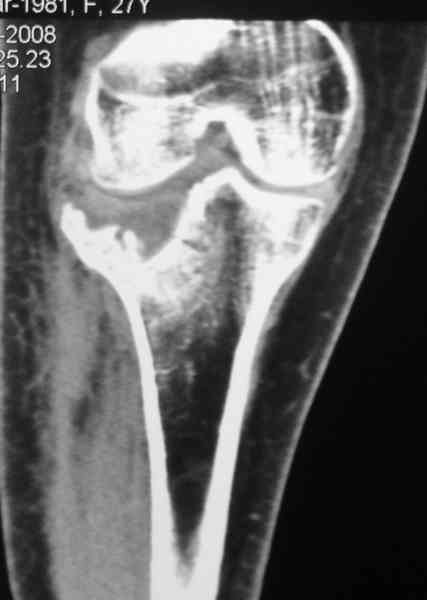

Есть ли возможность сделать КТ?

К большому сожалению КТ пока на ремонте, как запустять, сразу сделаю. Спасибо.

Уважаемый Абдурашид. Если нет противопоказаний , то из оперативных способов, я бы рекомендовал следующие: Полное замещение наружного мыщелка аллотрансплантатом либо открытая репозиция с элевацией и замещение дефекта ауто или аллокостью. В Ваших условиях , я бы рекомендовал второй способ. Во-время элевации необходимо разъединить фрагменты со стороны сустава ( надсечь скальпелем по линиям перелома, а затем тонким остеотомом их разъединить. При помощи долота произвести неполную остеотомию ( захватите не менее 1,5 - 2 см губчатой кости и поднять фрагменты, визуально отрепонировать и фиксировать 2-3 спицами. Дефект заместить костным ауто или аллатрансплантатом. Окончательная стабилизация пластиной ( лучше с угловой стабильностью, либо АВФ - позволит спокойно устранить угловую деформацию.

Недавно поступила больная через 1,5- 2 месяца.

Я согласен с мнением доктора Соломина, что необходимо выполнить СТ. Это поможет Вам не только определить степень повреждения твёрдых тканей, но и увадеть степень сращения. Без СТ не возможно планировать дальнейшую тактику лечения.

У пациента основной проблемой является импрессионый перелом наружного мыщелка, уже неправильно сросшийся, по-видимому. Аппаратом закрыто можно только подправить угол на уровне метадиафиза. Что

улучшит разве что внешний вид конечности, но не решит основной проблемы - грубой деформации суставной поверхности.

Через 3 месяца после перелома все еще можно выделить отломки, очистить от костной мозоли и и восстановить анатомию суставной поверхности. Фиксировать компрессионными шурупами. Важно помнить, что наружный мыщелок должен быть на 4-5 мм выше внутреннего. Передняя крестообразная связка обычно остается с частью кости и важно фиксировать ее проволокой по Ли. После восстановления суставной поверхности весь комплекс суставной поверхности нужно фиксировать к диафизу, можно использовать пластинку с фиксированными шурупами с наружной поверхности или две обычные с двух сторон или аппарат Илизарова. Важно сохранить задний наклон плато приблизительно 7 градусов. При закрытии доступа бугристость б.б кости фиксировать двумя шурупами. Важно добиться стабильности для максимально ранней разработки. Операция сложная, но интересная.